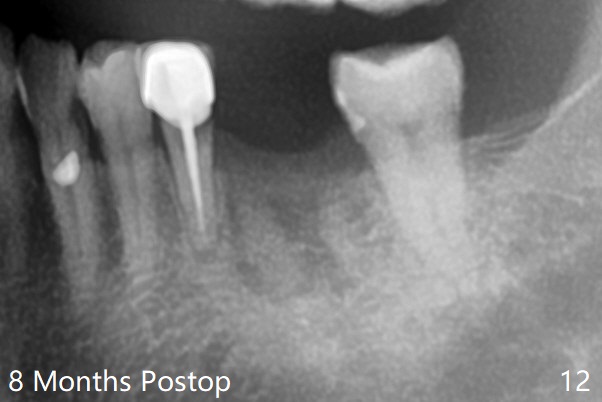

A 54-year-old man has distal (D) root fracture at #19 while the implant at #2 is osteointegrarting (Fig.1,2). Because of the large distal defect (Fig.3, after extraction), osteotomy (red line) will be initiated in the mesial socket (Fig.4, as distal as possible, with the coronal end in the middle of the socket) or the mesial slope of the septum (Fig.5) so that the implant (green) will be supported by the distally displaced septum (Fig.6 arrow). CT taken 8 months later confirms distal root fracture. A 6x11.5 mm or longer implant seems to be appropriate for the site (Fig.7). Three years later there is severe buccal swelling (Fig.8) with vertical mesial and distal root fractures (Fig.9). Although the buccal plate is lost, the septum remains (Fig.10 S), which will provide with blood supply to the bone graft (Fig.11), covered with Bioxclude and 6-month membrane and PSA suture. The bone density in the mesial and distal sockets is higher than that in the septum 8 months post cortical bone graft (Fig.12). In spite of bone graft, the buccolingual width reduces by almost 4 mm 8 months post extraction (Fig.3,4). In spite of bone graft, the buccolingual width reduces by almost 4 mm in 8 months post extraction (Fig.3,4). A 5x11.5 mm implant will be placed (Fig.15).